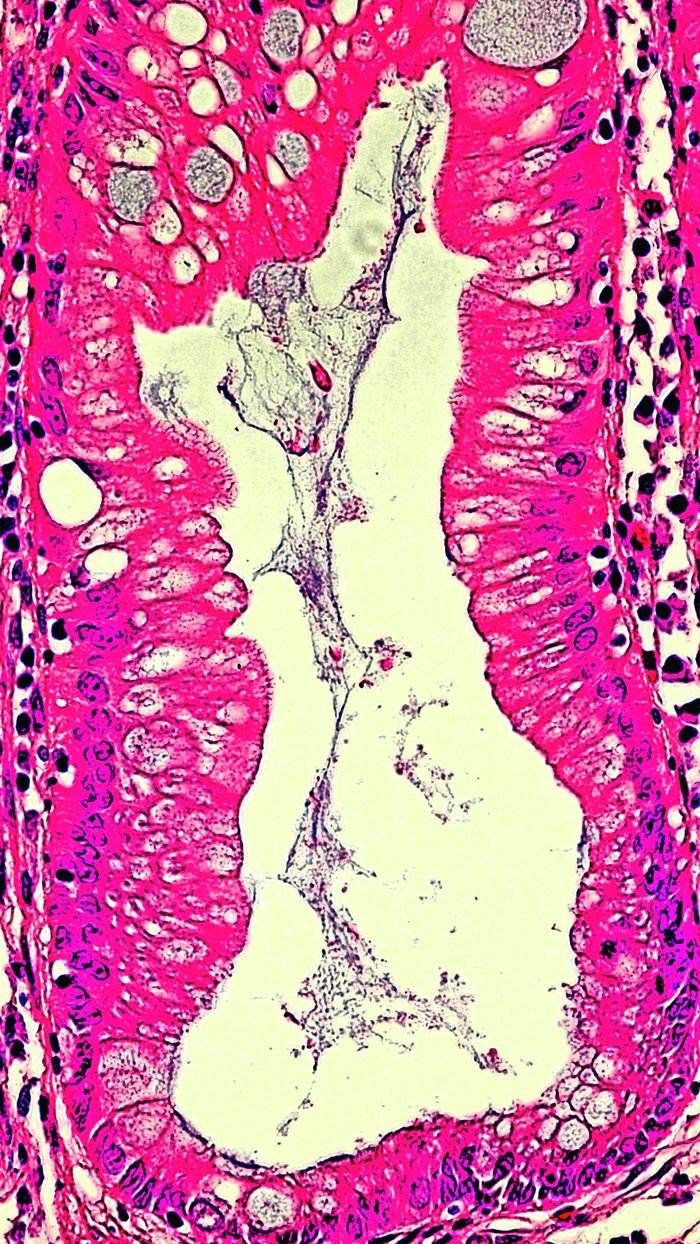

제목: 한반도 (2018)

조직소견: 대장용종

작품설명: 대장용종을 현미경으로 관찰하면 흥미로운 모습을 다양하게 볼 수 있다. 제주도를 포함한 한반도가 현미경 속에서 보인다.